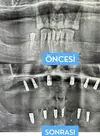

Implant tedavisi